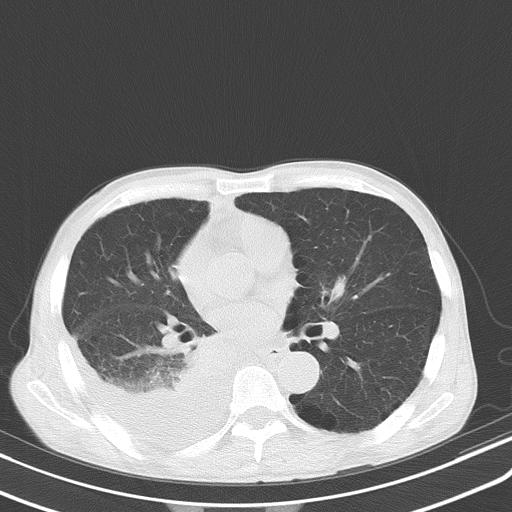

右肺继发型tb并右侧tb性胸腔炎,右侧胸腔大量积液并右下肺膨胀不全,慢支肺气肿、多发肺大泡。建议抽胸水实验室检查并复查排除恶性在占位。

右上肺继发型肺结核,右胸腔中等量积液。

左上肺大泡。

1)右肺继发型肺结核。2)左肺胸膜下多发性肺大泡。3)右侧胸腔积液。

右上肺继发型肺结核,右胸腔中等量积液。左上肺大泡。